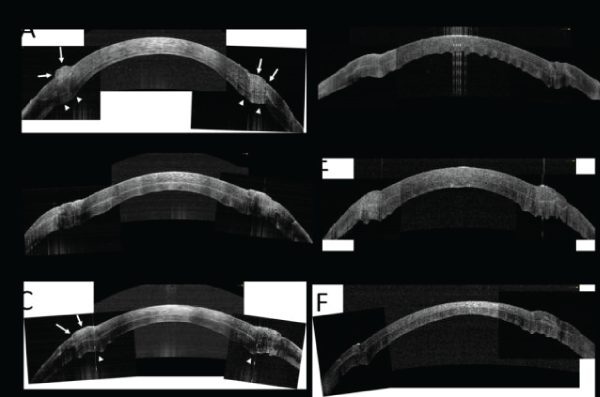

| Figure 3: OCT images after suturing in Pair 1 - Pair 6 (A-F). The central scans and side scans were montaged. We made measurements of the graft and host thickness at the center. A: In Pair ,graft and host thickness were 358 μm and 111 μm, respectively. At the suture zone, there were much anterior bulging and anterior surface mismatch (arrows), and posterior bulging (arrow heads). B: In Pair 2, graft and host thickness were 328 μm and 235 μm, respectively. The graft fit into the host side pocket with less bulging at the suture zone. C: In Pair 3, graft and host thickness were 252μm and 200μm, respectively. At the suture zone, there were much anterior bulging and anterior surface mismatch (arrows), and posterior bulging (arrow heads). D: In Pair 4, graft and host thickness were 295 μm and 234 μm, respectively. The graft fit into the host side pocket with less bulging at the suture zone. E: In Pair 5, graft and host thickness were 348 μm and 224 μm, respectively. The graft fit into the host side pocket with less bulging at the suture zone. F: In Pair 6, graft and host thickness were 174 μm and 208 μm, respectively. The graft fit into the host side pocket with less bulging at the suture zone. |